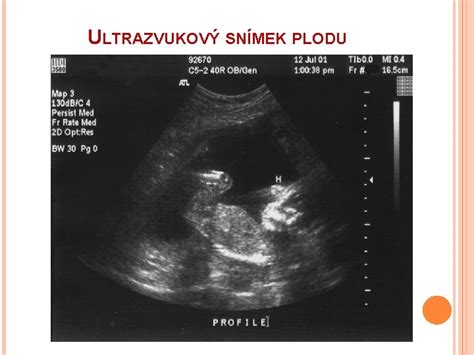

Vývoj bábätka v 11. týždni tehotenstva

V 11. týždni tehotenstva sa vaše bábätko už výrazne podobá na človeka. Embryonálne štádium je oficiálne ukončené a dieťa je teraz považované za plod. Meria približne 40-54 mm (CRL - od hlavičky po zadoček) a váži okolo 7-10 gramov.

- Pohlavné orgány: Aj keď sa pohlavie už rozhodlo pri oplodnení, vonkajšie genitálie sa vyvíjajú a od tohto týždňa sa začínajú líšiť u chlapčekov a dievčatiek. Na ultrazvuku však pohlavie ešte nie je spoľahlivo rozlíšiteľné.

V období medzi 11. a 13. týždňom tehotenstva čaká nastávajúce mamičky prvý ultrazvukový screening, známy ako "šijové prejasnenie" (nuchal translucency scan). Toto vyšetrenie je dôležité pre posúdenie rizika chromozomálnych abnormalít plodu.